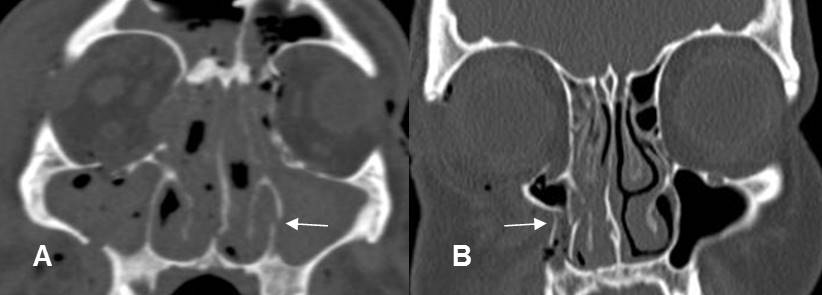

Fig 194. Lefort II.

A: TAC axial. Fractura de la lámina pterigoidea y el piso de la órbita derecha.

B: TAC reconstrucción coronal. Fractura no desplazada de la órbita. Adicionalmente hay fractura de la pirámide nasal derecha. (Flecha gruesa).

Fig 195. Lefort III.

A: TAC axial y B: TAC reconstrucción coronal. Múltiples fracturas en los antros maxilares y los rebordes orbitarios. En el lado derecho hay compromiso del piso de la órbita y el arco cigomático. (Flecha gruesa).